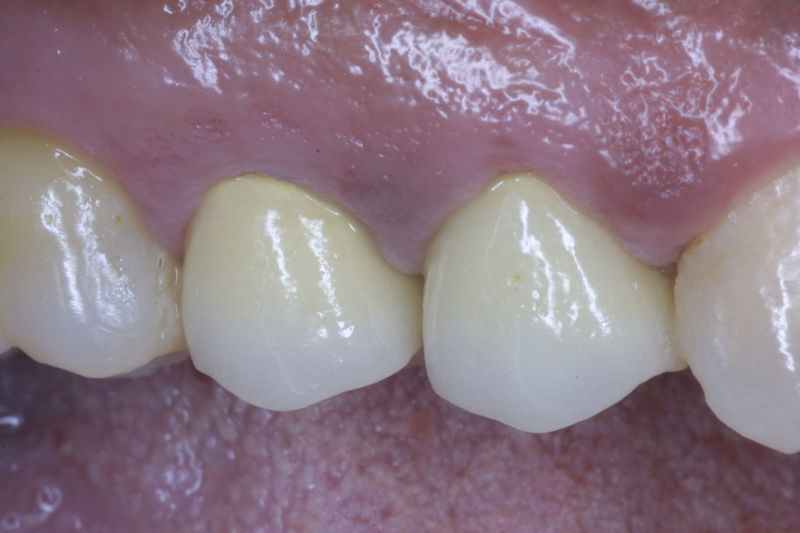

Restauraciones fabricadas en el laboratorio con materiales estéticos, los cuales cubren de manera total dientes anteriores y posteriores. Se utilizan primariamente para restaurar dientes con caries, fracturas y/o defectos amplios, así como soportes de puentes. Para poder enviar el caso al laboratorio se toman impresiones utilizando materiales de impresión o técnicas modernas digitales.